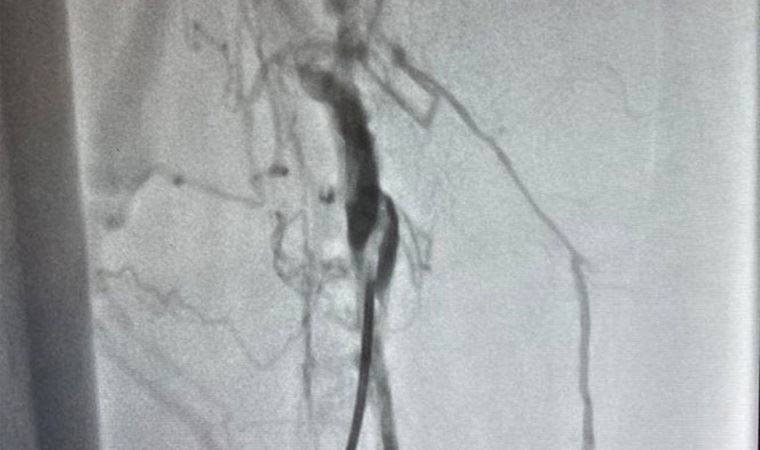

KEAH Kalp Damar Cerrahisi Bölümü A.B.D. Öğretim Üyesi Dr. Burak Tamtekin ve ekibi, 77 yaşında yaşlı bir hastanın bacakta oluşan pıhtının önce kalbe, daha sonra akciğere atması sonucu hayati tehlikesi oluşabilecek hastaya, herhangi bir kesi yapılmadan, narkoz verilmeden, anjiyo yöntemi ile risksiz bir şekilde, toplardamarda oluşan pıhtı çıkarma işlemi yaptı.

NARKOZ VERİLMEDEN ANJİYO YÖNTEMİ

Ameliyatsız yöntemle ilk kez böyle bir operasyon yapıldığını söyleyen Tamtekin, “İleri derecede bacağının şiş ve yürüyemez bir halde hastanemize gelen 77 yaşındaki Hakan amcanın bacağının şiş ve yürüyemez bir durumda olduğunu gördük. Yaptığımız ilk muayenesinde bacak toplardamarlarında oluşan pıhtıları gördük. Bacakta oluşan pıhtıları çıkarmak için öncelikle karın içine bir filtre yerleştirildik. Daha sonra pıhtı dolu damarın içine girip, bacakta biriken pıhtıları özel bir aygıtla parçalayıp dışarı çıkardık. Narkoz verilmeden anjiyo yöntemiyle yaptığımız bu başarılı operasyonla akciğere pıhtı atmasını da bu uyguladığımız yöntemle önlenmiş olduk" dedi.